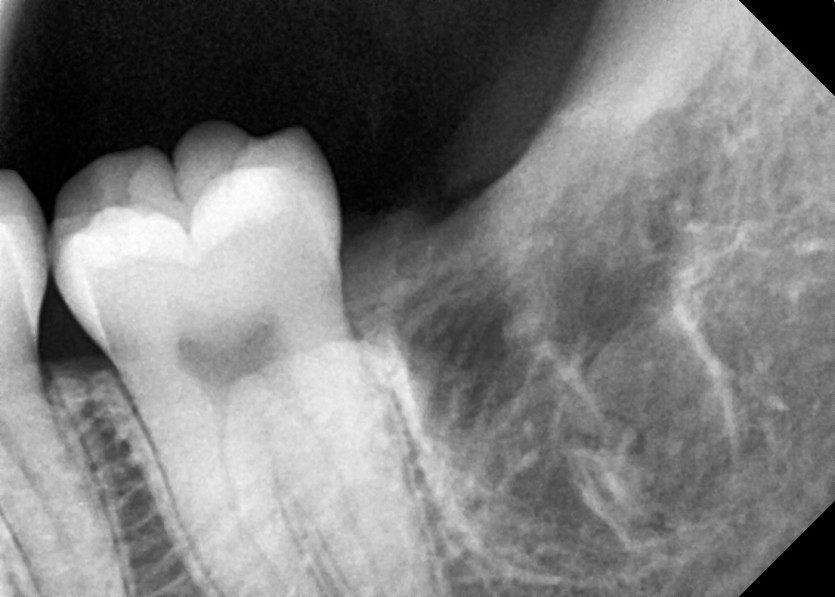

#18,28,38,48 사랑니 발치

구강 외과 전문의가 당일 발치했습니다.